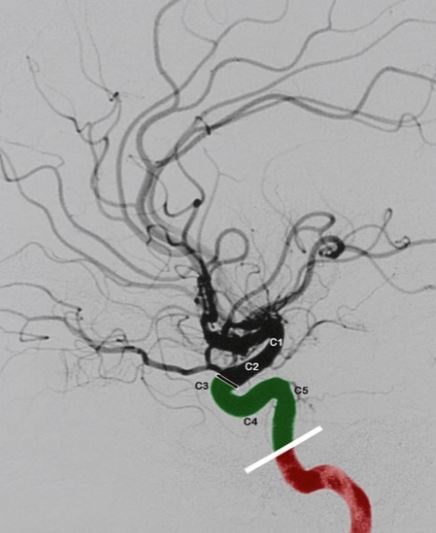

• Anterior circulation Brain